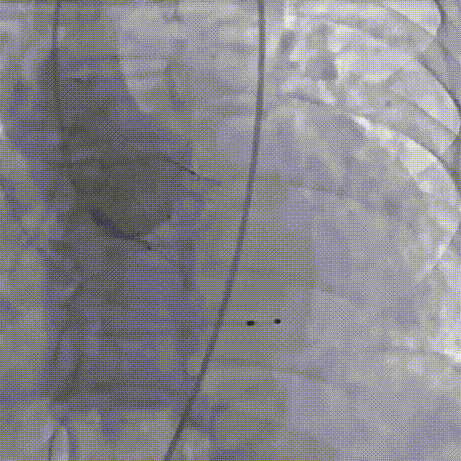

2026年伊始,TaurusTrio经导管主动脉瓣系统在复旦大学附属中山医院,浙江大学医学院附属第二医院,中国医学科学院阜外医院,首都医科大学附属北京安贞医院,四川大学华西医院等多家临床中心成功开展上市后全国首批植入。这不仅是TaurusTrio正式走向广泛临床应用的重要里程碑,更标志着中国单纯主动脉瓣反流介入治疗正式迈入了“心键合璧”的全新纪元。